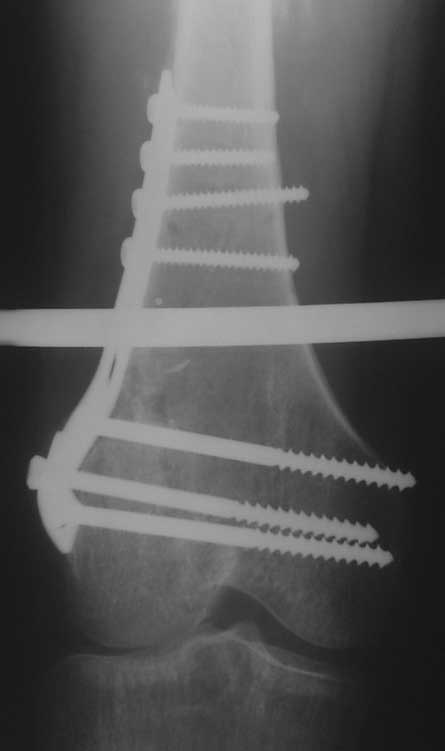

Уважаемые коллеги, помогите пожалуйста с тактикой лечения. Больная 43 лет, подвернув правую ногу, получила простой (А2) перелом правого бедра в с\3, м\у установленными ранее пластинами. В течении 4 недель лечится методом скелетного вытяжения.В анамнезе: в июне 2011г. получила перелом наружного мыщелка правого бедра на фоне консолидированного в порочном варусном положении перелома вертельной зоны (со слов травма 5 лет назад - лечилась консервативно), сопровождающимся укорочением 5 см. В одну операционную сессию выполнен остеосинтез перелома мыщелка бедра Т-образной пластиной и с целью коррекции укорочения выполнена вальгизирующая межвертельная остеотомия с фиксацией клинковой пластиной.На наш взгляд, наиболее простым является накостный остеосинтез диафизарного перелома по передней поверхности бедра, но смущает необходимость образования в последующем дополнительного кожного рубца. Пожалуйста, может быть у Вас есть другие мнения. Зарание благодарен. С уважением А.Гринь. ОКБ №2 г.Тюмень.

На снимке положение клинка идеальное, но шейка в ротации. Из-за неправильного расчета остеотомии не удалось латерализовать диафиз, и конечность находится в чрезмерном вальгусе. При укорочении с вальгусом увеличивает стресс в зоне между пластинами, и конструкция не выдерживает, и при малой травме может осложниться стрессовым переломом.

Расположение клинка и степень сращения в зоне остеотомии трудно увидеть по одной проекции, и поэтому желательно дополнить исследования КТ и боковыми рентген снимками.

Из возможных операций: я бы предложил провести ретроградную фиксацию бедра после удаления дистальной пластины. При отсутствии полного сращения перелома можно установить пару шурупов спереди и сзади гвоздя, или можно оставить укороченный вариант пластины.